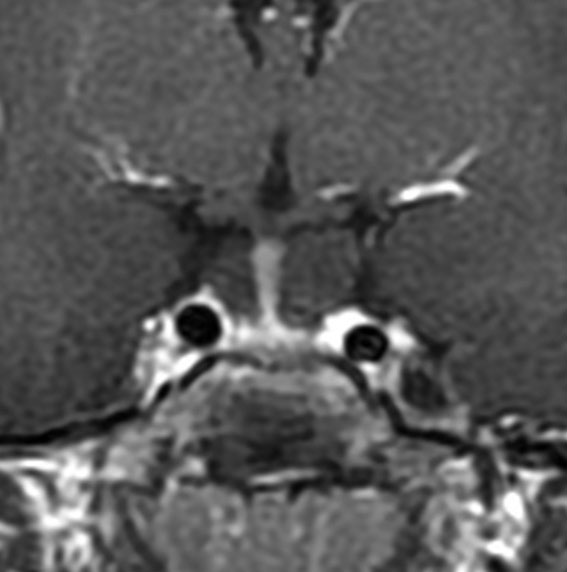

11際の小児です。トルコ鞍が拡大しています。下垂体柄が伸びていますが下垂体は正常で,鞍上部にのう胞があります。通常のラトケのう胞が下垂体中間葉から発生するので,鞍隔膜下腫瘍になりますが,これは鞍隔膜の上にある腫瘍(鞍上部腫瘍)に分類されます。無症状なので経過を見てもいいのですが,このタイプはおそらく年余の経過で増大傾向をたどり,まだ低年齢なのでいずれ手術治療となります。経鼻手術でのう胞をつぶすこともできるのですが,再発の確率は高いでしょう。従って,根治をめざす開頭手術で,のう胞壁全摘出を行います。

前頭側頭開頭 pterional approachで全摘出しました。発生母地は下垂体柄前面でしたが完全摘出しました。術後に下垂体機能は正常に保たれています。病理所見は一層の上皮細胞でのう胞壁が構成されることが特徴です。これをラトケのう胞と呼ぶかどうか議論のあるところで,おそらく正確には内胚葉のう胞 endodermal cystと診断します。